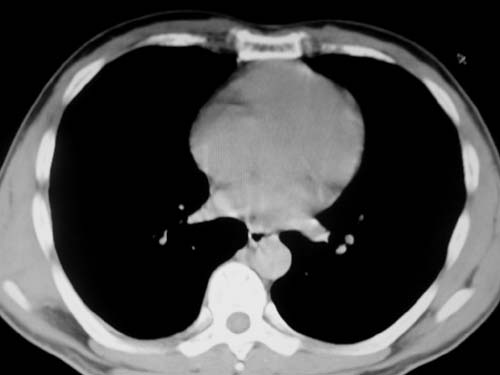

标题: CT19540: 31岁。自述结核性胸水治疗两个月后,在外院拍x线发 [打印本页]

标题: CT19540: 31岁。自述结核性胸水治疗两个月后,在外院拍x线发

右侧胸壁结节状软组织影伴相应肺叶内受侵,伴右侧胸腔积液。考虑:结核性可能大。

右侧胸壁结节状软组织影伴相应肺叶内受侵,伴右侧胸腔积液,结合临床,首先考虑结核。

考虑结核性胸膜炎,胸膜肥厚,不除外胸膜间皮瘤可能,建议复查。

1)考虑右侧结核性胸膜结节。2)右侧胸膜增厚+包裹性胸腔积液。

结核性脓胸、肺内结核?